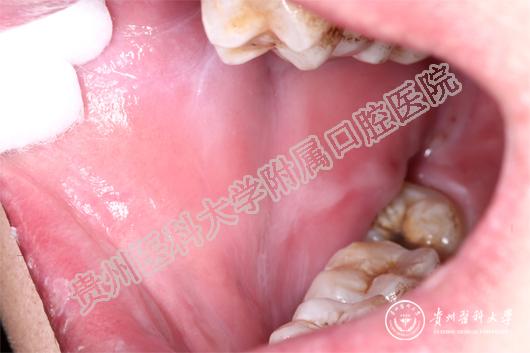

(患者治疗前后的口腔黏膜病损对比 上图:治疗前,下图:治疗1周后)

当天值班的王珣主治医师为小邓这一特殊病人加号,并作了相关检查后诊断小邓为药物引起的“过敏性口炎”。王珣介绍:小邓来的时候已经很严重了,上下唇、手背、拇指已经出现红色斑块,并且全口黏膜溃烂、生殖器可见不规则糜烂面。像小邓这种情况根本无法进食、而且疼痛难忍。若不及时救治,很有可能造成电解质紊乱。随后王珣医生询问病史发现:原来,5天前,小邓因智齿冠周炎自行服用了“消炎片”,随后出现全口黏膜溃烂,无法进食而且说话都困难,随后皮肤上也起红斑,生殖器也开始溃烂,疼痛难耐,无法入睡,人也明显消瘦了许多。

王珣叮嘱患者停用可疑药物,并为他对症用药。由于“过敏性口炎”的病情发展变化较大,王珣医生还为患者留了自己的微信,以便实时了解小邓的病情变化。1周后,小邓复诊时口腔生殖器黏膜已经痊愈,上下唇及手背、拇指的斑块也基本消退。小邓非常感谢太阳成集团tyc33455cc官网附属口腔医院,在疫情的特殊时期能为他开通绿色通道,让他的疾病痊愈 。